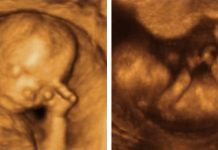

Ecografía 4D de 12 semanas

Ecografías 4 D: ¿Para qué sirven?

Recordemos los momentos del embarazo en los que es aconsejable realizar una ecografía, en este caso, en 2D: - En el primer trimestre, en la...